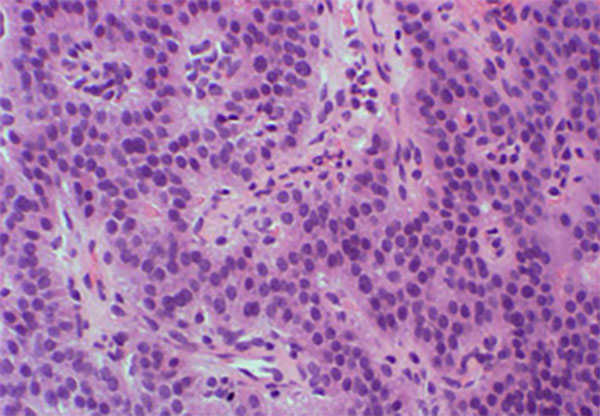

NETとNECの病理組織像の違い

膵NEC

異型核が見られ比較的豊富な細胞質を有する腫瘍細胞が活発に増殖しています。